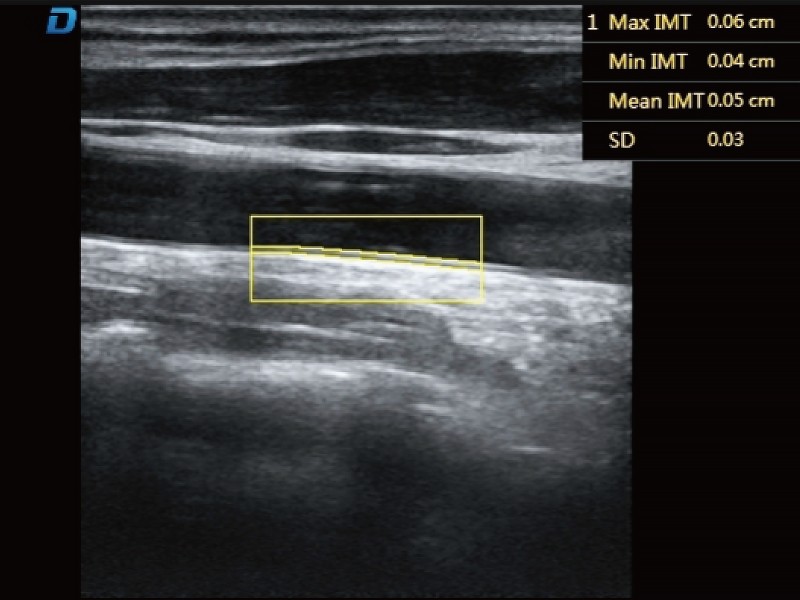

自動IMT